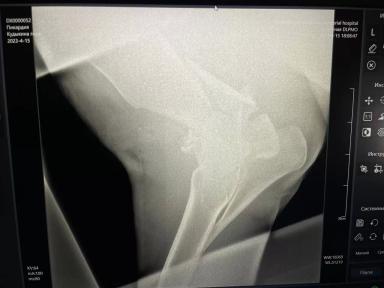

С другой стороны, мучить тоже сильно не хочется... Прошу совета и опыта! На фото 4 дня с перелома предплечья.